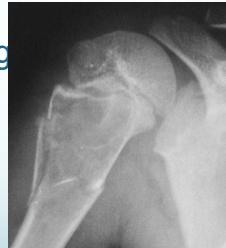

Giant-Cell Tumor

- Unknown origin:

- Giant cells abundant

- Behavior:

- One third benign

- One third locally aggressive

- One third (less) with distant metastasis

- Young adults

- Common sites:

- Around knee

- Proximal humerus

- Distal radius

Radiological Features

- Eccentric lesion:

- Radiolucent

- Soap bubble

- Abuts (adjacent) against the joint

- Thin cortex

- Margins may be clear / unclear:

- Depends on aggressiveness

- Treatment:

- Curettage & bone grafting

- More wide excision in recurrent and aggressive lesions